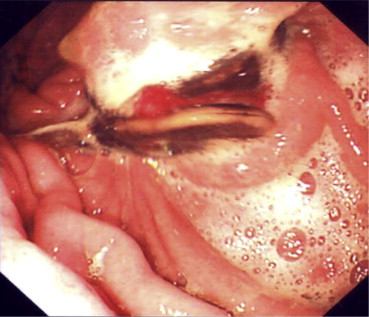

Preoperative upper gastrointestinal endoscopy showing erosion of the gastric ...

Figure 2.

Preoperative upper gastrointestinal endoscopy showing erosion of the gastric band into the lumen of the stomach.

After 1 year, the patient complained of continuous abdominal pain which was not relieved with usual analgesia. An attempt to remove the band endoscopically under general anesthesia was performed (Fig. 2). Because of lack of special endoscopic instruments, the intraluminal endoscopic removal of the band has failed. The patient underwent laparoscopic removal of the band through four ports. The band was eroding the anterior wall of the stomach and protruded into the lumen. Adhesiolysis was performed. The posterior wall of the stomach was intact. Incision through a healthy scar-free area in the anterior wall of the stomach was performed to access the gastric lumen. The band was cut and removed. The incision of the anterior wall of the stomach, and the defect produced by the eroding band were closed in two layers using 00 nonabsorbable sutures. The integrity of the repair was examined by endoscopic air insufflation of the stomach and by methylene blue test. The postoperative period was uneventful. Three months after surgery, the patient was free of pain and tolerated normal diet. The patient’s weight was within average levels. She preferred to be kept on diet control rather than undergo a gastric bypass operation as a secondary weight-reducing operation.